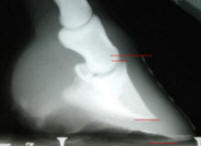

These are

tough radiographs to see, but this is a beautiful case, so I put them

up, anyway. the attending vet diagnosed a 14 degree rotation and full

sole penetration of P3. |

I just

now had the follow-up radiographs taken, after four years of total

comfort. This horse is very comfortably ridden 3-4 times a week, and is

as happy as a horse can get. |

Another grazing muzzle, a few

less trips to the feed store, routine natural hoof care and another

wonderful horse snatched from the edge of the grave!!! This is really

fun!